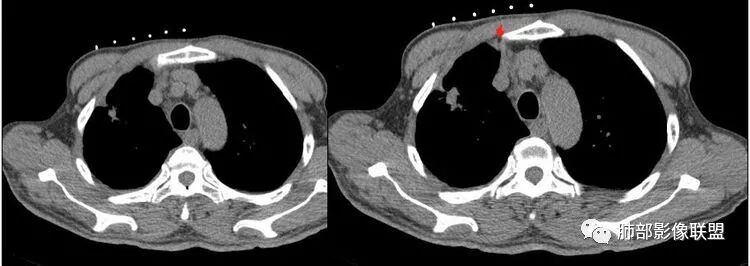

傅昌瑜:老年男性,有贲门癌史,右上团块影分叶毛刺胸膜凹陷→恶性可能,周围有卫星灶→良性可能。右侧胸廓塌陷,右侧胸膜有较多结节,双侧胸腔少量积液。整体考虑良性可能→结核可能性大。建议增强及穿刺检查。

THINKER:右上肺前段结节,胸膜凹陷征,整体收缩,有空泡征,胸膜多发结节,纵隔淋巴结肿大,双侧胸腔少量积水;考虑恶性,原发腺癌>转移;

红日东升:老年男性,贲门癌病史。右肺尖段病灶,收缩明显,多发毛刺,胸膜牵拉,局部胸膜增厚牵拉,周围卫星灶,右上叶体积较小。考虑炎性肉芽肿,结核可能,鉴别腺癌。

深分叶、边缘膨隆、胸膜凹陷征及附近多发结节,胸膜不干净,纵隔多发淋巴结

感觉胸膜上有很多结节,层面不够,还有一点胸水。

南边:纵隔淋巴结有融合的迹象,边界不清,右侧内乳动脉增粗了很多;怀疑纵隔淋巴结用血很大。有结核的话并不代表不能得癌肿;一般情况下结核附近的病灶呈条索树芽状;综上所述恶性不能完全排除。

这种纵隔右移提示病程较长,腔静脉后见轻度增大淋巴结。